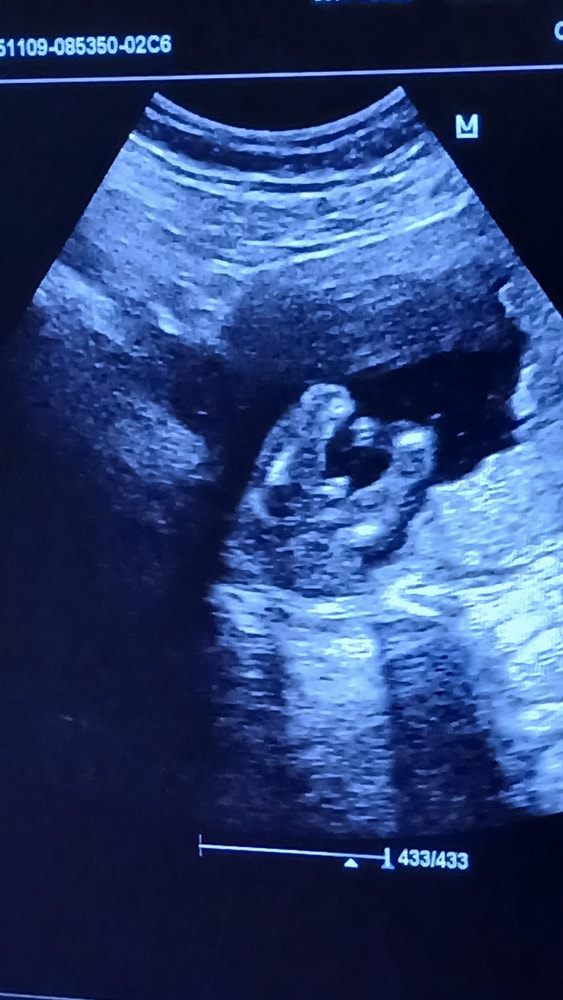

У меня два замечательных сына, сейчас в ожидании чуда 🤰

на первом узи в 12 недель врач сказал у вас девочка (но конечно верить не могу на первом узи, так как в 12году с сыном до 3 скрининга говорила девочка, а со вторым в принципе все время говорили мальчик, один раз не поняли кто 😅)

на втором узи в 20 недель врач дал конверт в котором было написан